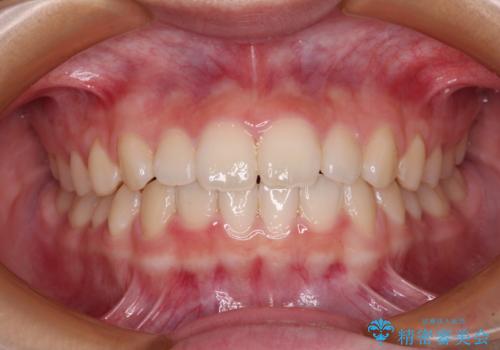

- 前歯のデコボコを気にして来院された高校生の患者様です。

捻れた前歯が前方に飛び出している点も気になっており、目立たない装置を希望されたため、インビザラインを用いて矯正治療を行うこととしました。

上下ともに少し捻れが残っていたため、治療の継続を提案しましたが、本人も親御さんも満足とのことで、治療を終えました。

捻れの改善により突出感も改善されました。